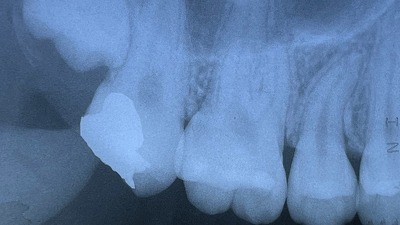

患者さんは20歳の女性。他院で次回抜髄と言われ、母親と来院しました。

治療後のレントゲンです。

この症例は無麻酔下でラバーダムとマイクロスコープを使用して2時間治療に要しました。費用は4万円+消費税でした。幸いにも治療後の炎症も起きずに十数年経過しています。この症例を考察します。